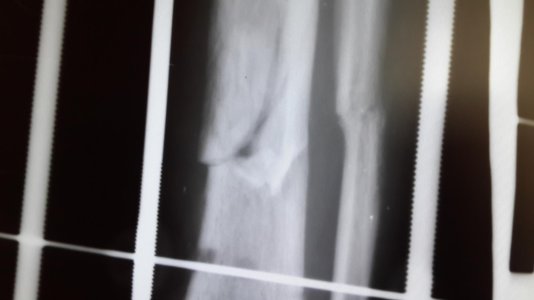

Здравствуйте доктор мне 26 лет , 29 июля 2016 года я получил травму на соревнования открытый перлом голени бб и мб кости , 12 августа поставили аппарат илизарова , 12 ноября сдела снимок костная мозоль слабая нормально ли это? с 16 ноября начал наступать на ногу даю вес 30кг , до этого не наступал

добавил снимки сделанные 29сентября и 12 ноября